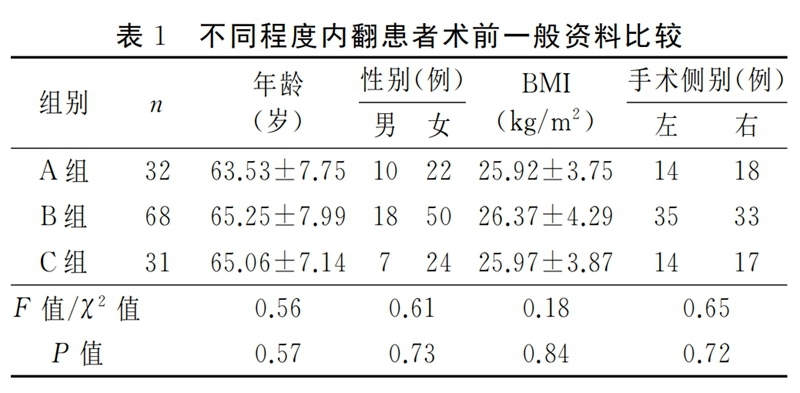

纳入本研究的患者均获得随访,随访时间12~30个月,平均随访时间(19.01±3.80)个月,术前A组、B组、C组三组患者在性别、年龄、BMI及手术侧别等方面无明显统计学差异,见表1。UKA手术前后HKA、OKS评分、VAS评分、ROM情况见表2。UKA术前术后对比,膝关节功能明显改善,差异有统计学意义(P<0.05)。

2.2 组间比较

三组患者的术前OKS、VAS及膝关节ROM比较差异有统计学意义(P<0.05)。组间两两比较,A组与B组的术前OKS和膝关节ROM比较差异无统计学意义(P>0.05),C组分别与A组、B组的术前OKS及膝关节ROM比较,差异有统计学意义(P<0.05);A组分别与B组、C组的术前VAS比较差异有统计学意义(P<0.05),B组与C组的术前VAS比较差异无统计学意义(P>0.05)。三组患者的术后HKA比较差异有统计学意义(P<0.05)。组间两两比较,A组与B组的术后HKA比较差异无统计学意义(P>0.05),C组分别与A组、B组比较差异有统计学意义(P<0.05)。三组患者末次随访时的OKS、VAS及膝关节ROM比较,差异无统计学意义(P>0.05),见表3。